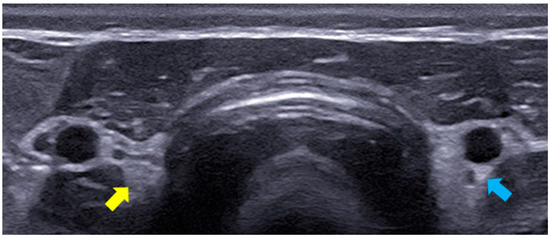

2.3. B-Mode Thyroid Ultrasonography

The B-mode ultrasound study of the thyroid was performed using the MyLabTM X8 Platform equipment (Esaote, Firenze, Italy), with a 4–15 MHz multi-frequency and linear transducer. The settings for gain, frequency, focus, time gain compensation (TGC), and depth were adjusted according to the physical characteristics of each dog participating in the study. The lobes of the thyroid gland were identified in their typical location, situated between the sternocephalic and sternothyroid muscles, ventral to the trachea and caudal to the larynx. Both were evaluated in a longitudinal manner with regard to their dimensions (length and width) and echogenicity in relation to the adjacent muscles (hypoechoic, isoechoic, or hyperechoic) and surface regularity. The aforementioned characteristics were also assessed in the transverse section, except for the dimensions (Figure 1). Figure 2 presents the right thyroid lobe on B-mode ultrasound in a longitudinal section of a female dog.

Figure 1. The B-mode ultrasound image of the right (yellow arrow) and left (blue arrow) thyroid lobes of a 9-year-old female dog.